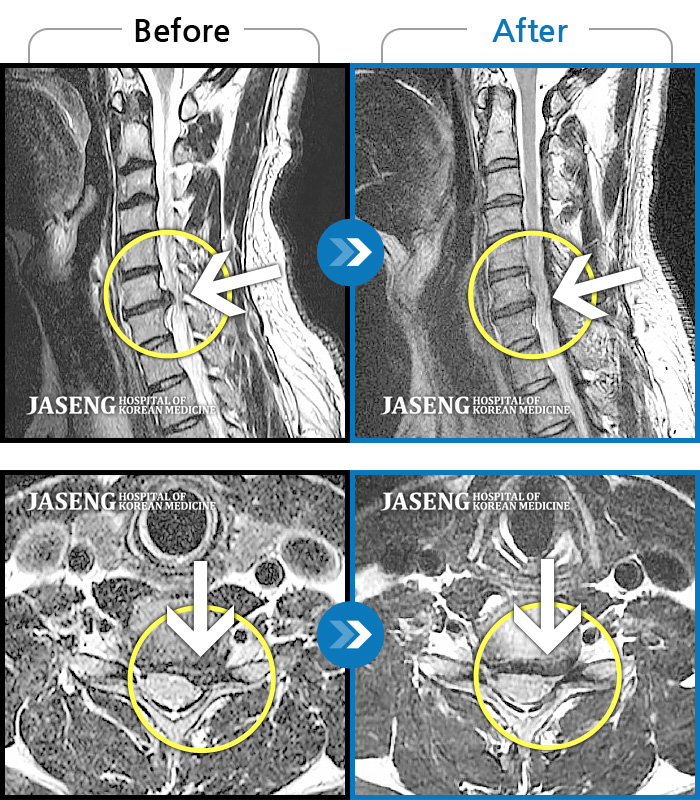

목디스크

강남 · 강만호 원장

양측 승모근 통증과 목 통증, 견갑골 통증으로 고개를 돌릴때 통증을 호소하는 환자였습니다.

촬영시기

2019.11.18 ~ 2024.07.30

2024.08.09